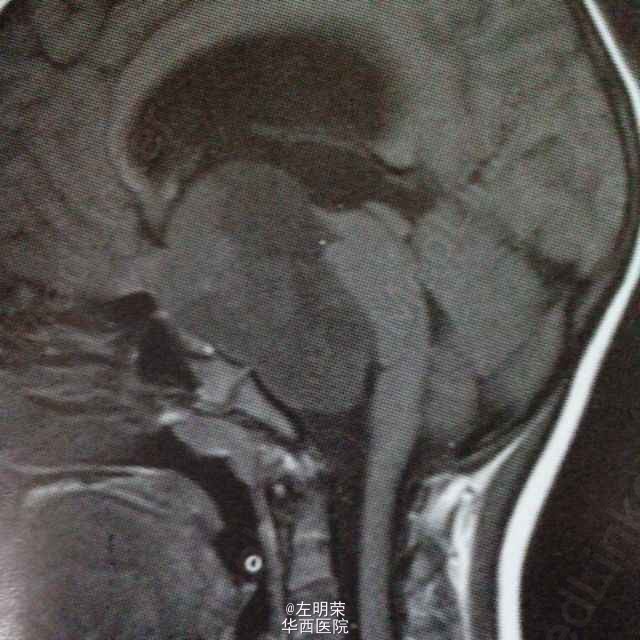

女,6岁,以间断头痛3个月余,加重2个月之主诉入院。MRI示:桥前池-鞍上池-三脑室内巨大不规则均匀强化影,鞍背骨质可见破坏,病灶内可见囊变坏死区。可见脑干及病灶周围实质明显受压移位,病灶与脑实质分界清楚;考虑诊断脊索瘤,颅咽管瘤,神经鞘瘤。术中见肿瘤囊实性,血供丰富,边界尚清,位于鞍背上方,脑干前方,与基底动脉,大脑后动脉粘连紧密,给予全部切除;病理示:神经鞘瘤。